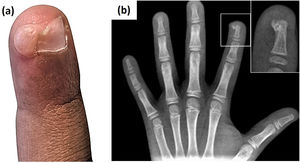

Un niño de 8 años acudió 4 meses después de la aparición de un nódulo eritematoso y friable de 1cm en la falange distal del segundo dedo de la mano izquierda. No presentaba antecedentes de traumatismo. Con base en las características clínicas de la lesión se asumió el diagnóstico de granuloma piógeno y se realizó el curetaje de la lesión. El estudio histopatológico era inespecífico. Dos semanas más tarde presentó un nódulo de 1cm de color carne con elevación de la uña y onicólisis en la misma zona (Fig. 1a). La radiografía confirmó el diagnóstico de exostosis subungueal, revelando una proyección calcificante en la parte dorsal de la falange distal (Fig. 1b). Se procedió a la resección quirúrgica de la lesión.